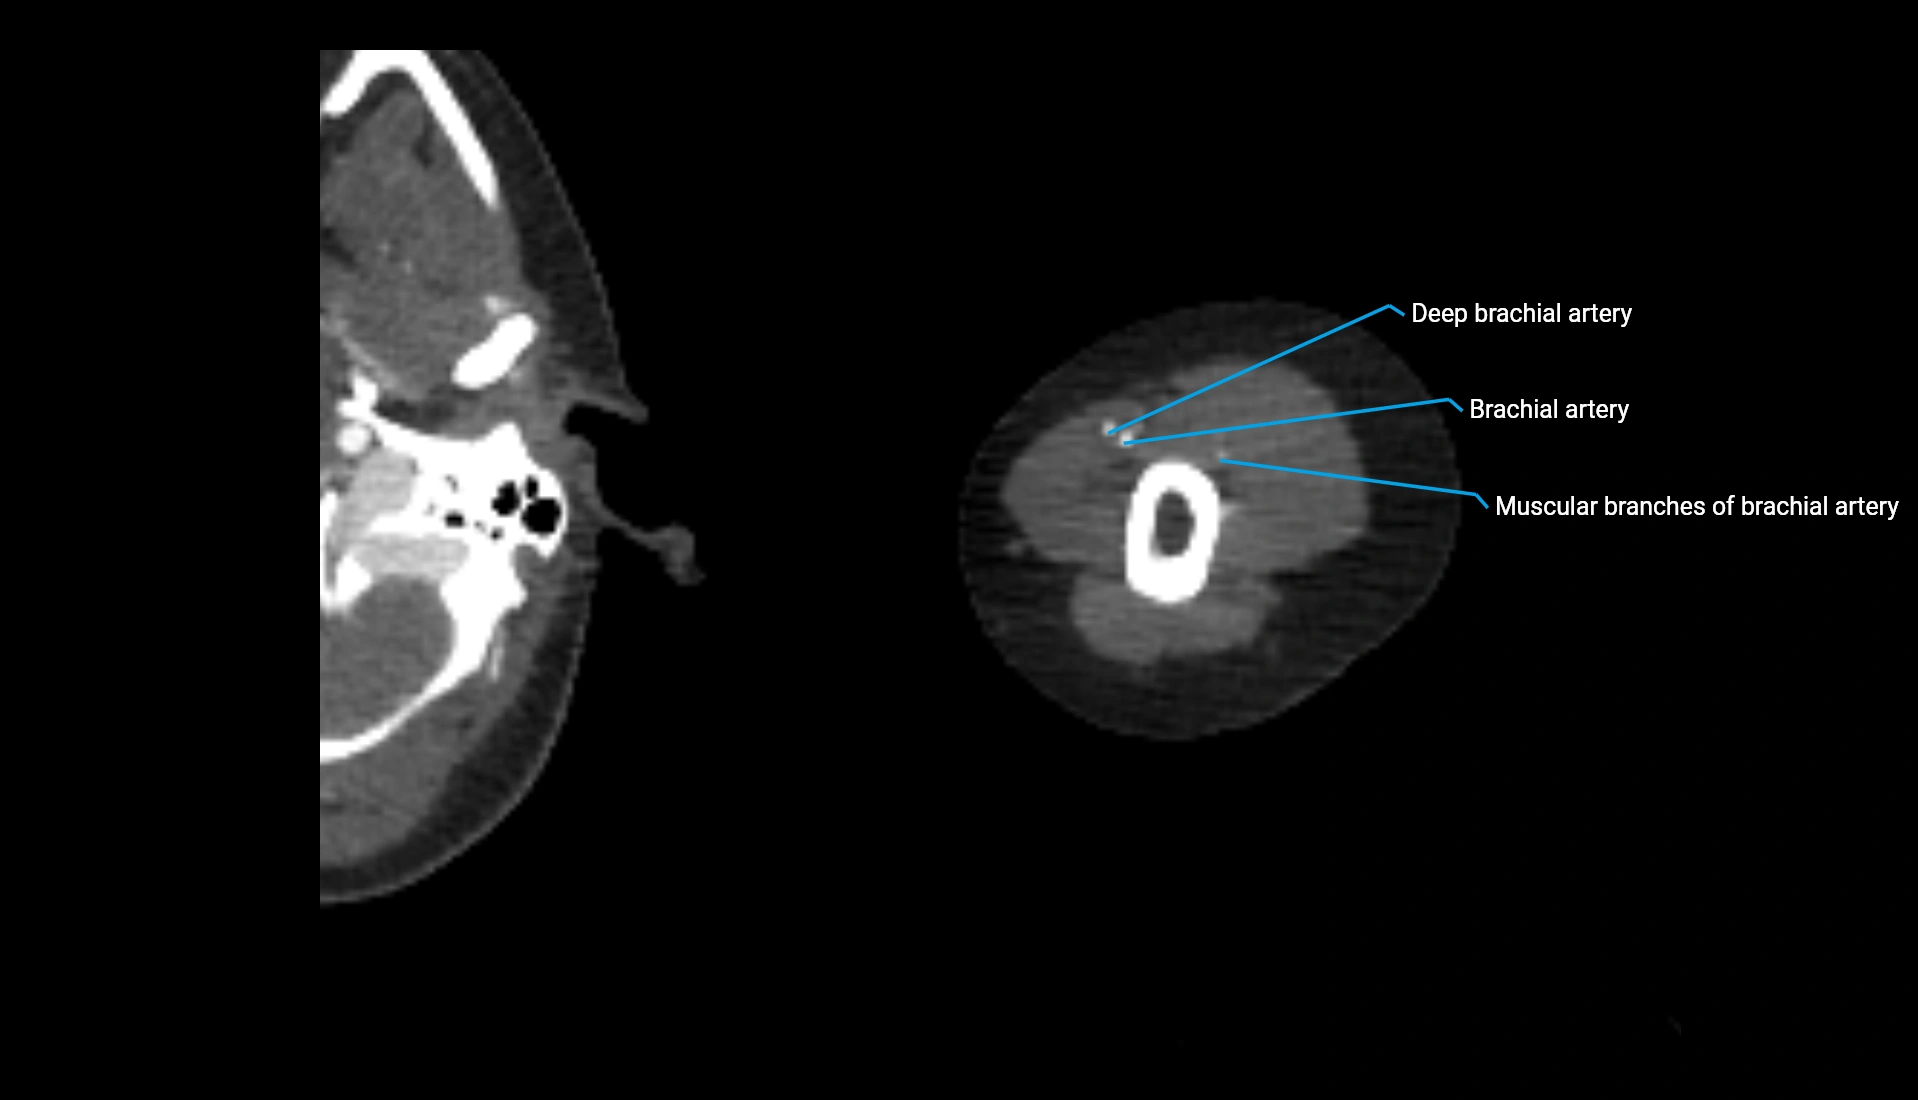

MRI image

image